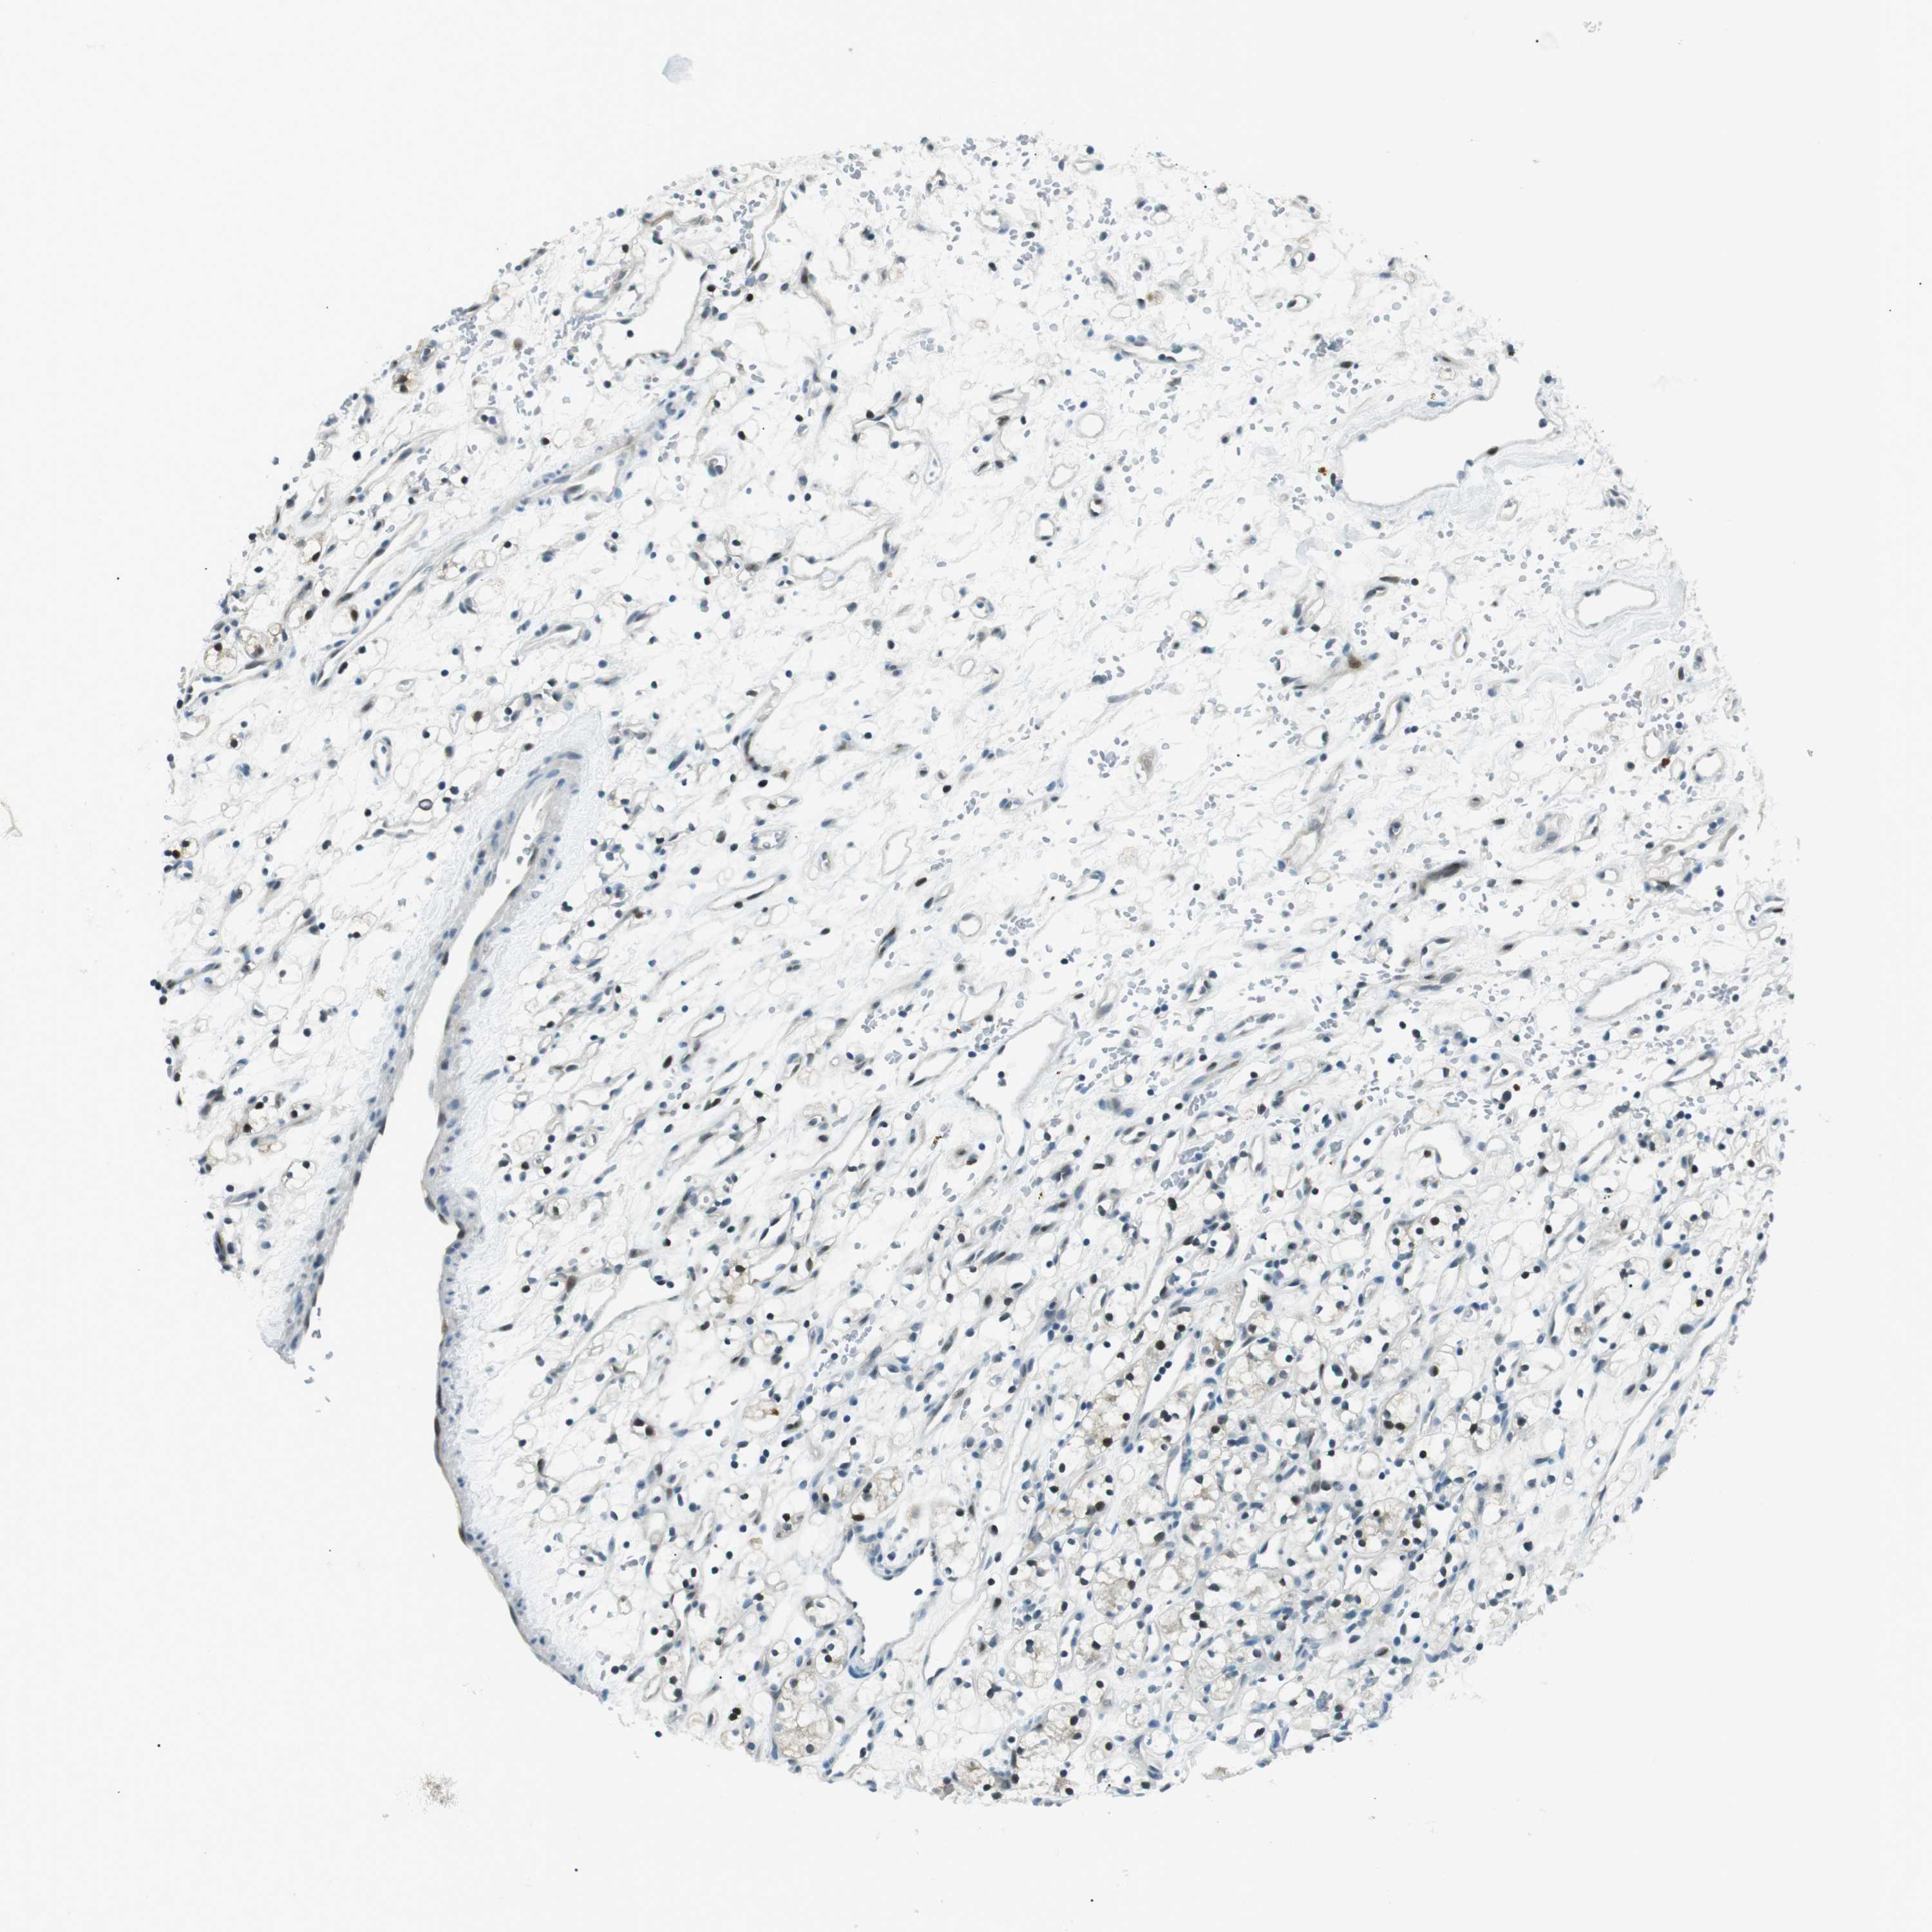

KIDNEY RENAL CLEAR CELL CARCINOMA (VALIDATION) - Interactive survival scatter ploti

The Survival Scatter plot shows the clinical status (i.e. dead or alive) for all individuals in the patient cohort, based on the same data that underlies the corresponding Kaplan-Meier plots. Patients that are alive at last time for follow-up are shown in blue and patients who have died during the study are shown in red.

The x-axis shows the expression levels (FPKM) of the investigated gene in the tumor tissue at the time of diagnosis. The y-axis shows the follow-up time after diagnosis (years). Both axes are complimented with kernel density curves demonstrating the data density over the axes. The top density plot shows the expression levels (FPKM) distribution among dead (red) and alive patients (blue). The right density plot shows the data density of the survived years of dead patients with high and low expression levels respectively, stratified using the cutoff indicated by the vertical dashed line through the Survival Scatter plot. This cutoff is automatically defined based on the FPKM cutoff that minimizes the p-score. The cutoff can be changed by dragging the vertical line or by entering a cutoff value in the square labeled "Current cut-off".

Under the Survival Scatter plot the p-score landscape (black curve; left axis) is shown together with dead median separation (red curve; right axis). Dead median separation is the difference in median mRNA expression between patients who have died with high and low expression, respectively. It is calculated as follows: median FPKM expression of dead patients with high expression - median FPKM expression of dead patients with low expression. This is intended to aid the user in visually exploring custom cutoffs and the associated p-scores and dead median separation.

Individual patient data is displayed and can be filtered by clicking on one or more of the category buttons on the top of the page. Categories describing expression level and patient information include: high, low, alive, dead, female, male and tumor stages. The scale of the x-axis can be toggled between linear and log-scale by clicking on the "x log" button. Mouse-over function shows TCGA ID, patient information and mRNA expression (FPKM) for each patient.

& Survival analysisi

Kaplan-Meier plots summarize results from analysis of correlation between mRNA expression level and patient survival. Patients were divided based on level of expression into one of the two groups "low" (under cut off) or "high" (over cut off). X-axis shows time for survival (years) and y-axis shows the probability of survival, where 1.0 corresponds to 100 percent.

PJA1 is not prognostic in Kidney Renal Clear Cell Carcinoma (validation)

Best expression cut offi

: 11.59

Average pTPM 15.1

Number of samples 100